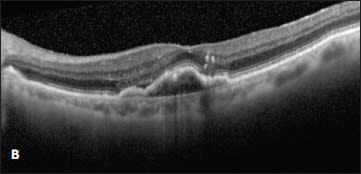

Figure 1. (top) A patient with a new occult CNV with PED and subretinal fluid was treated with two monthly intravitreal injections of ranibizumab with flattening of the PED and resolution of the SRF (bottom).

Case 1. This case involved a 92-year-old woman who presented with a new occult lesion in the left eye. Prior to her conversion, her baseline vision was 20/40. Despite new CNV with a PED and subretinal fluid noted on OCT, her vision remained unchanged (Figure 1). She was treated twice with intravitreal ranibizumab with dramatic resolution of the PED and subretinal fluid.

Figure 2. A new occult CNV with PED (A). After treatment with bevacizumab, OCT showed persistent subretinal fluid (B). The therapy was switched to ranibizumab, and after nine injections, the PED had slightly grown in size, but the subretinal fluid had resolved (C). Due to PED growth, the patient was switched to aflibercept, and after two injections, the subretinal fluid resolved, and the PED flattened (D).

Case 2. The second case involved a 99-year-old woman who presented with a new occult lesion in the left eye. There was loss of one line of vision at 20/40, and a new PED with associated subretinal fluid was noted on her OCT (Figure 2A). She was treated with three doses of monthly bevacizumab with a minimal response, and her vision declined to 20/50+2 (Figure 2B).

She was then switched to monthly ranibizumab. The subretinal fluid resolved with one injection, and her vision improved to 20/30. However, after nine injections of monthly ranibizumab, her vision declined to 20/40, with a small amount of intraretinal fluid and an enlarging PED (Figure 2C). This visit coincided with the commercially availability of aflibercept, and the treatment was changed to monthly 2.0 mg aflibercept. After two injections, her vision improved to 20/30, the PED flattened, and the subretinal fluid resolved (Figure 2D).